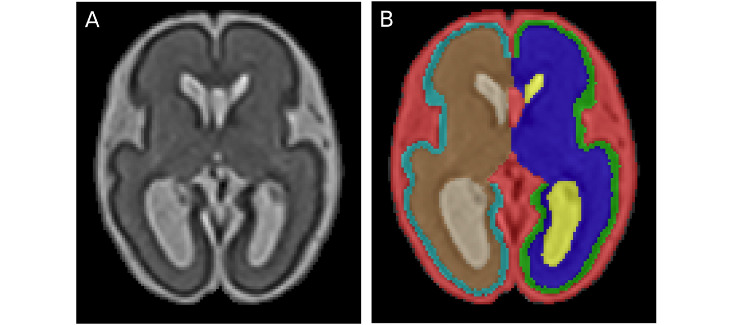

Esta investigación ha tenido como objetivo principal el estudio de la ventriculomegalia aislada no severa y su relación con el grado de desarrollo cortical cerebral. El estudio del cerebro mediante técnicas de imagen juega un papel crucial a la hora de entender las anomalías cerebrales y el diagnóstico precoz. Es muy importante estudiar las anomalías cerebrales en el útero y la evaluación de las desviaciones en caso de un mal desarrollo. En este trabajo se utilizaron imágenes de resonancia magnética cerebral a partir de 23 fetos humanos con diagnóstico de ventriculomegalia aislada no severa y 25 controles sanos, entre las 26 y 29 semanas de gestación, para identificar desviaciones del plegamiento de la corteza cerebral relacionadas con la ventriculomegalia y el desarrollo neurológico.

* En la imagen: Fetal brain MRI segmentation: 26.4 GW-old fetus with right INSVM (A) and corresponding segmentation (B), with different labels for left and right WM, cortex and lateral ventricles.